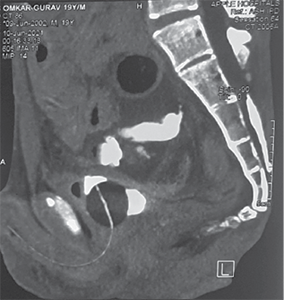

He was resuscitated with 1 500 ml of crystalloids through a left subclavian central line. Contrast-enhanced CT of the abdomen revealed perforation of the urinary bladder and extravasation of free urine into the pelvic cavity. It also revealed pneumointestinalis and grossly dilated bowel loops till mid transverse colon. There was a cut-off point at the level of the mid transverse colon (Figure 1).

Figure 1. Contrast enhanced computed tomography abdomen pelvis showing A – axial view showing dilated ascending colon, proximal transverse colon, intraperitoneal fluid collection B – extravasation of urine inside peritoneal cavity with pelvic collection